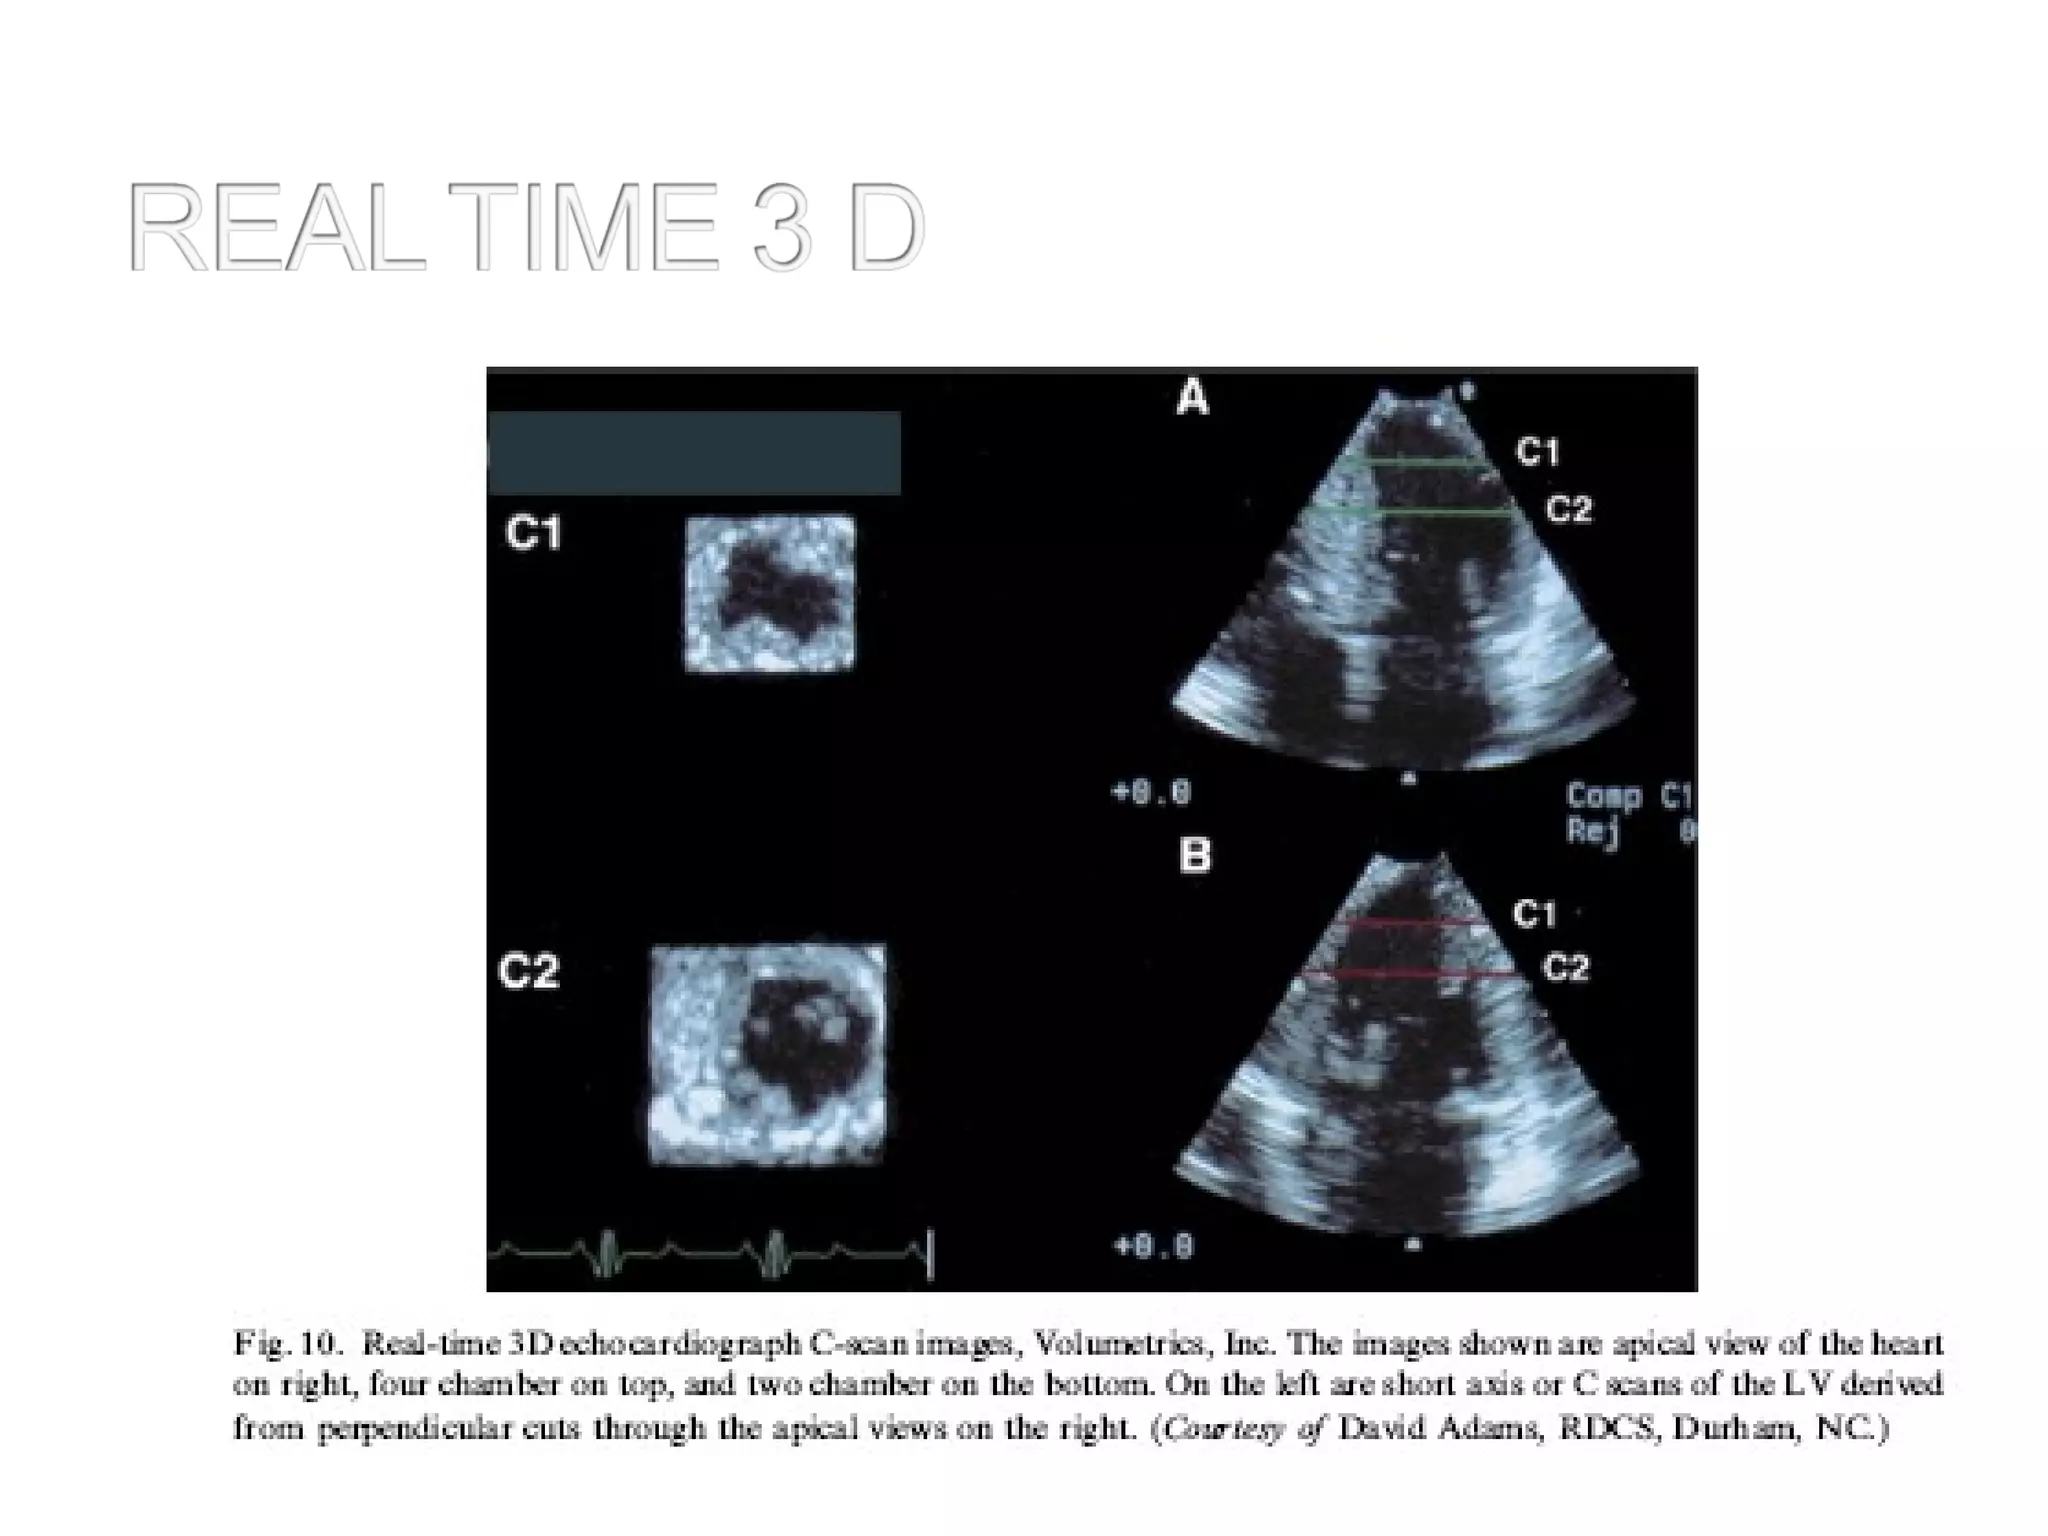

• One of the most significant developments of

the last decades was the introduction of 3-

dimensional (3D) imaging and its evolution

from slow and labor-intense off-line

reconstruction to real-time volumetric imaging

• The major proven advantage of this

technique is the improvement in the accuracy

of the echocardiographic evaluation of

cardiac chamber volumes.

• Another benefit of 3D imaging is the realistic

and unique comprehensive views of cardiac

valves and congenital abnormalities

• Display of 3D information

1.A 3D data set consists of bricks of pixels

called volume elements or voxels

• A process known as cropping can be used

to cut into the volume and make some

voxels invisible

• 3D data sets of voxels are turned into 2D

images in a process known as volume

rendering